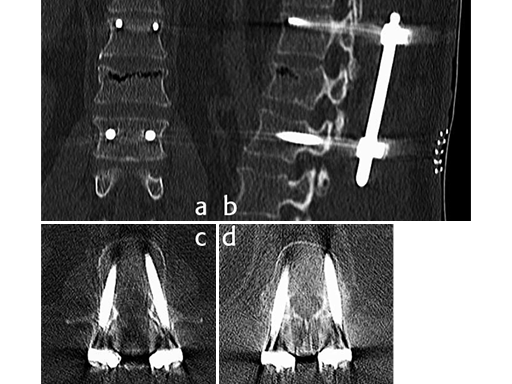

X-rays and CT scans were performed for preoperative analysis, definition of the fracture type and surgical pre-op planning.

The lateral x-ray and CT scans showed a typical wedge deformity of the fractured vertebral body (L1). The fracture included the cranial endplate as well as the anterior and posterior wall.

Using the USS Fracture MIS system for the initial stabilization allowed for a minimally invasive approach with intraoperative active reduction of the spinal fracture. The unique design of the fracture clamp allowed for independent correction of the sagittal alignment (Fig a) as well as height readjustment (Fig b).